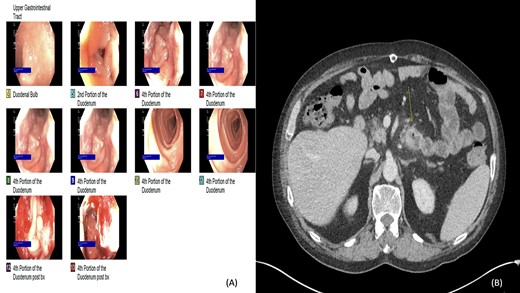

We present a case of a 74-year-old male who presented in 2018 with abdominal pain and underwent a series of cross-sectional imaging (CT-scan) which revealed an obstructed left bile duct and an associated mass. Follow-up esophagogastroduodenoscopy (EGD) and endoscopic ultrasound (EUS) confirmed the presence of a mass at the confluence of the bile ducts with possible liver invasion (Fig. 1A). A needle aspiration done was suspicious for carcinoma. Patient underwent diagnostic laparoscopy which revealed no evidence of metastatic disease, therefore, an extended left hepatectomy with a roux-en-y hepaticojejunostomy was performed. On pathological evaluation of the specimen, invasive mucinous adenocarcinoma with an intraductal papillary mucinous component, in a background of high-grade dysplasia was found involving the left hepatic lobe (Segment 4b) and left hepatic duct (Fig. 1B). Surgical margins were negative for carcinoma. No lymphovascular, perineural or lymph node involvement was seen. The tumor was classified as pT1a, pNx R0 according to the American Joint Committee of Cancer (AJCC) 8th edition.

(A) Computed tomography (axial): ovoid low-density mass contiguous with dilated left hepatic bile duct. (B) Histology: invasive mucinous adenocarcinoma with an intraductal papillary mucinous component, in a background of high-grade dysplasia was identified involving the left hepatic lobe (segment 4b) and left hepatic duct.